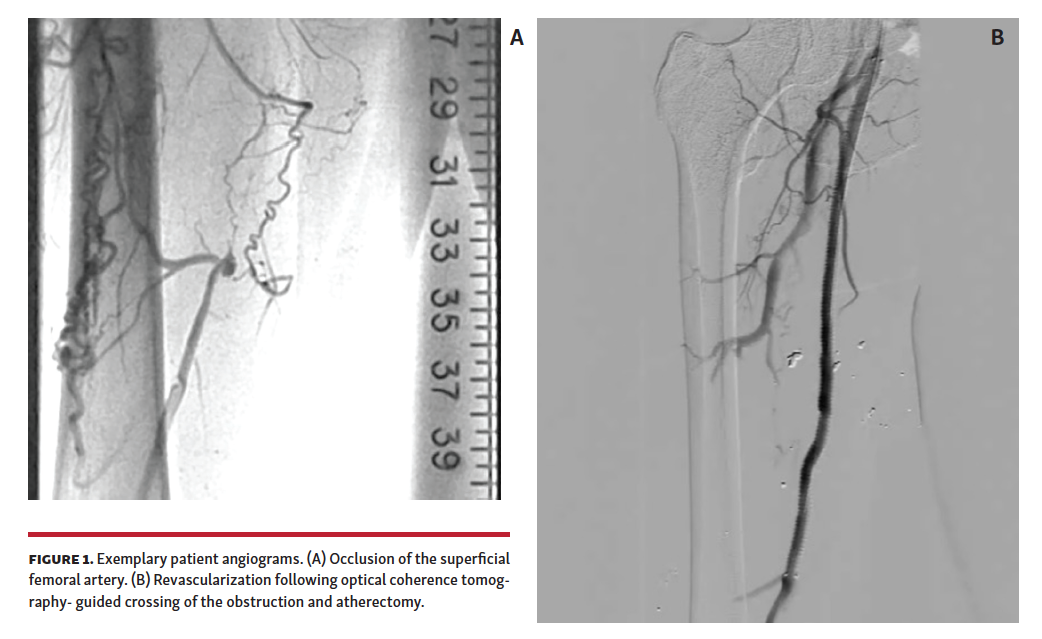

The pilot phase of the HIPACT study was a prospective assessment of histologic samples obtained from patients who underwent atherectomy of obstructive lesions in FP arteries. Patients were eligible for the study if they had chronic PAD (Rutherford-Becker categories 2–5) and occlusions within a FP segment (Figure 1). Patients were ineligible if they were taking oral anticoagulants, had a history of contrast allergy, or had undergone attempted treatment or atherectomy of the target CTO previously. Patients returned to the clinic within 6 months after the procedure for symptom assessment, ankle-brachial index evaluation, and documentation of any repeat procedures since treatment.

The patients were prepared for surgery following standard procedures. The target lesion was identified by angiography and its length was documented. With the lesion identified, the occlusion was traversed with an Ocelot crossing catheter (Avinger) (Figure 2) and then subsequently treated with TurboHawk directional atherectomy (Medtronic). Excised tissue was captured in the nosecone of the atherectomy device and collected at the end of the procedure, fixed in 10% neutral buffered formalin following standard methodology, and sent to the pathology lab.

A total of 19 patients participated in this pilot phase of the HIPACT study; they were predominantly male (67%) with a mean age of 72 ± 11.6 years. The CTO lesions were primarily (67%) in the superficial femoral artery (SFA), with 4 in a popliteal artery, and 1 each in the tibial peroneal trunk and the common iliac artery. All obstructions were crossed successfully by the crossing catheter with no dissections or perforations. Directional atherectomy reduced the obstructions such that blood flow was restored through the area of the obstruction, as determined by angiography. The amount of fluoroscopy time varied with the device used, with less than a minute of time (14 seconds) needed when the OCT-guided catheter was advanced through the obstruction to prepare a path for the atherectomy device (Figure 3).